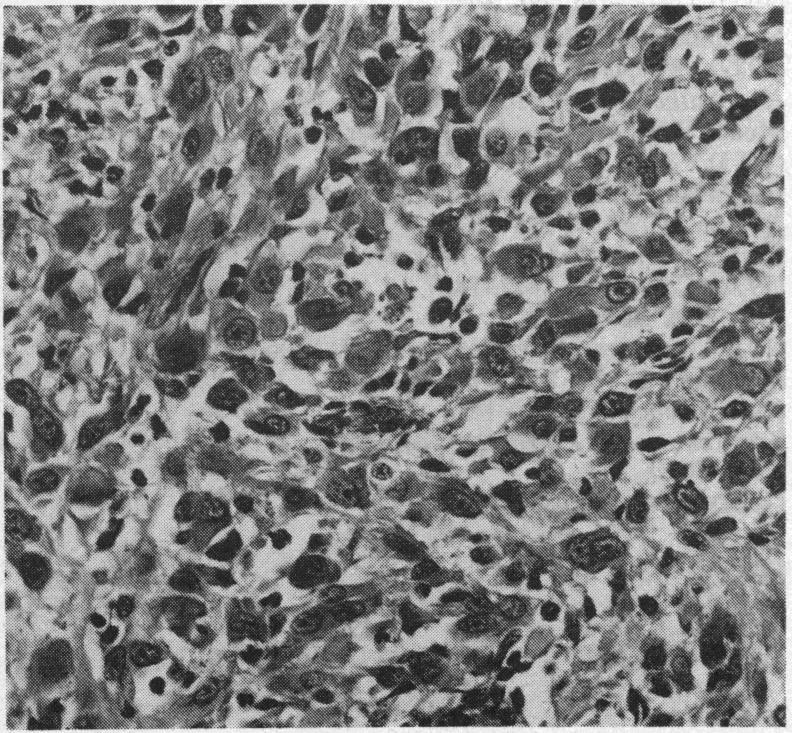

Epithelioid sarcoma of Enzinger.

J R Soc Med. 1984;77 Suppl 4(Suppl 4):24-6.